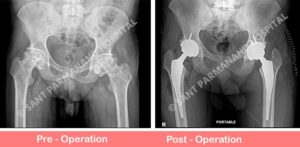

Primary Complex Total Hip Replacement

26 years old young gentleman with known disease of anklosying spondylitis involving spine and hip joint. On xray evaluation hip joint was in end stage arthritis and patient was not able to sit and walk. Thus planned for hip replacement surgery.

These complex cases require meticulous preoperative planning in terms of ... Read more..